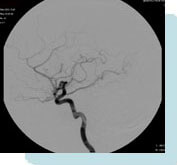

Special Procedures or Interventional Radiography is a growing subspecialty in which both vascular and nonvascular diseases are diagnosed and treated. It is a minimally invasive technique that utilizing small catheters and catheter-based instruments. These procedures are performed with local or intravenous sedation and are guided by radiological imaging such as flouroscopy, CT or ultrasound.

- Diagnostic Angiography and Venography